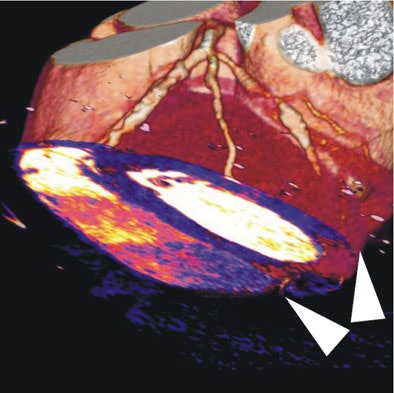

| In a 64-year-old man with chest pain, colored regions of blood-pool images represent iodine, while the darker parts of the myocardium depict ischemia as a lack of contrast uptake. Arrows indicate the myocardial blood-pool deficit, i.e., ischemia. |

| In a 64-year-old man with chest pain, image of the corresponding slice shows inferior ischemia (arrows). |